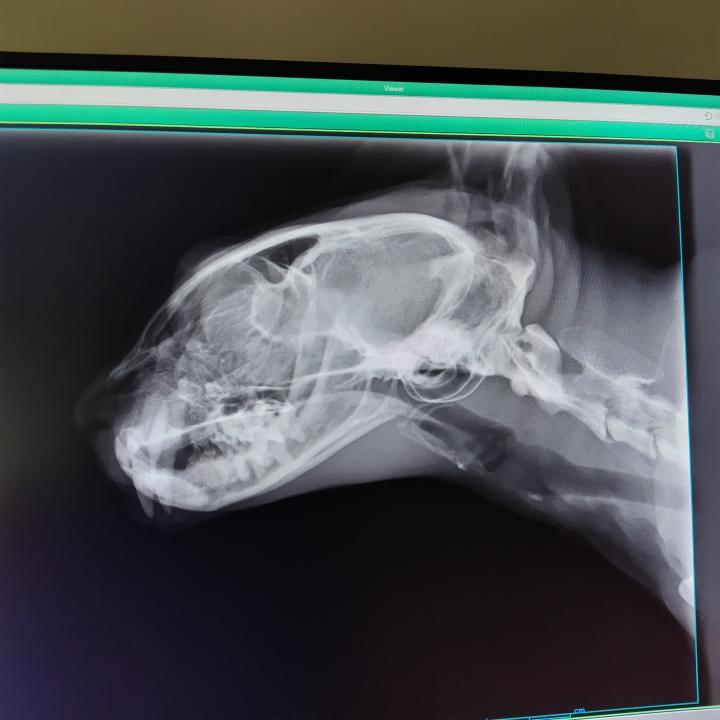

二週間に一度の検診時にレントゲン撮ってきました

横から

変な影もなく、見た目問題ないので

次に血が混じるなら、本格的な検査と

止血剤を考える事になりました